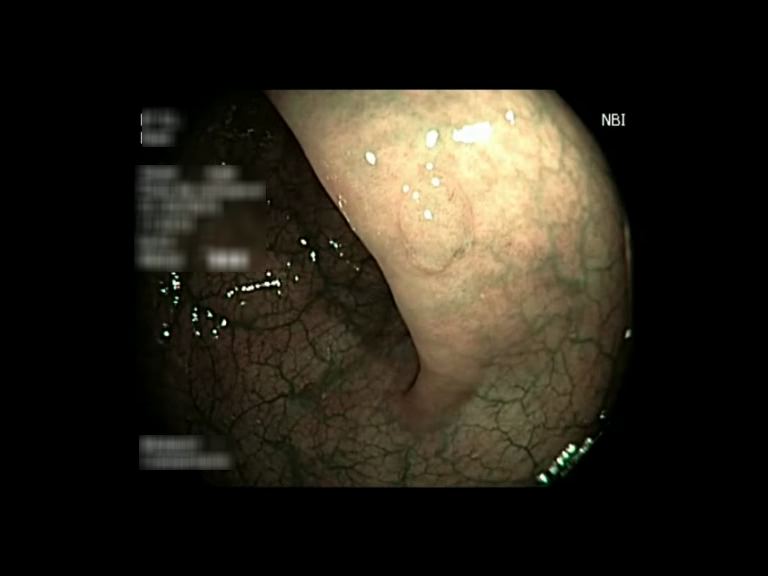

| Lesion | White Light Frame | NBI Frame | White Light Video | NBI Video | Camera Calibration |

| serrated_01 |  |

|

WL.mp4 | NBI.mp4 | cam.xml |